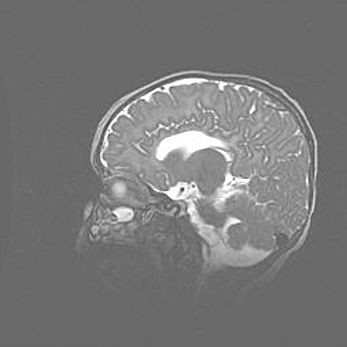

Аномалия Денди-Уокера. Признаки гипоплазии мозолистого тела.

Возраст: 5 месяцев 3 дня

Вес: 5550 г

Пол: мужской

Окружность головы: 39 см

Срок гестации: 40 недель

Аномалия Денди-Уокера – это порок развития головного мозга, для которого характерна триада симптомов: гипотрофия или аплазия червя мозжечка и/или полушарий мозжечка, расширение четвёртого желудочка с формированием ликворной кисты задней черепной ямки, гипертензионная гидроцефалия различной степени.

Гипоплазия мозолистого тела относится к дефектам внутриутробного этапа развития мозговой ткани, возникающим в процессе закладки структур головного мозга, что происходит на начальных этапах развития эмбриона.